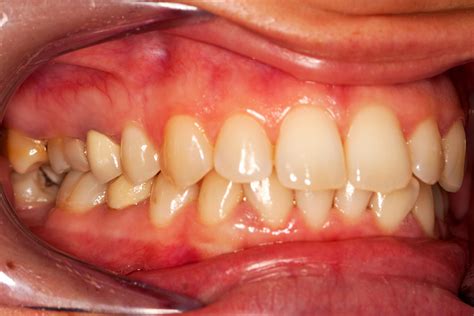

When gingivitis develops, these characteristics change noticeably. The most obvious visual sign is a change in color—gums affected by gingivitis often appear red or dark red, sometimes even purplish in severe cases. This redness is caused by increased blood flow to the inflamed tissue. The gums may also look shiny or glossy rather than having their normal matte appearance, and they lose their firm texture, becoming soft and puffy instead.

• Swollen or puffy gums: The gum tissue appears enlarged and may extend further over the teeth than normal

As gingivitis progresses to a moderate stage, the symptoms become more pronounced. The redness spreads from the gum line to cover more of the gum tissue, and swelling becomes more obvious. Bleeding occurs more frequently and with less provocation—you might see blood in the sink after normal brushing. The gums may start to pull away from the teeth slightly, creating small pockets where bacteria can accumulate. Bad breath becomes more persistent and noticeable.

In advanced gingivitis, the visual changes are unmistakable. The gums appear bright red or purple, significantly swollen, and may feel spongy to the touch. Bleeding occurs easily and frequently, sometimes even spontaneously. The gum tissue may begin to recede noticeably, exposing more of the tooth surface and potentially the root. At this stage, without intervention, gingivitis is on the verge of progressing to periodontitis, which involves bone loss and is irreversible.